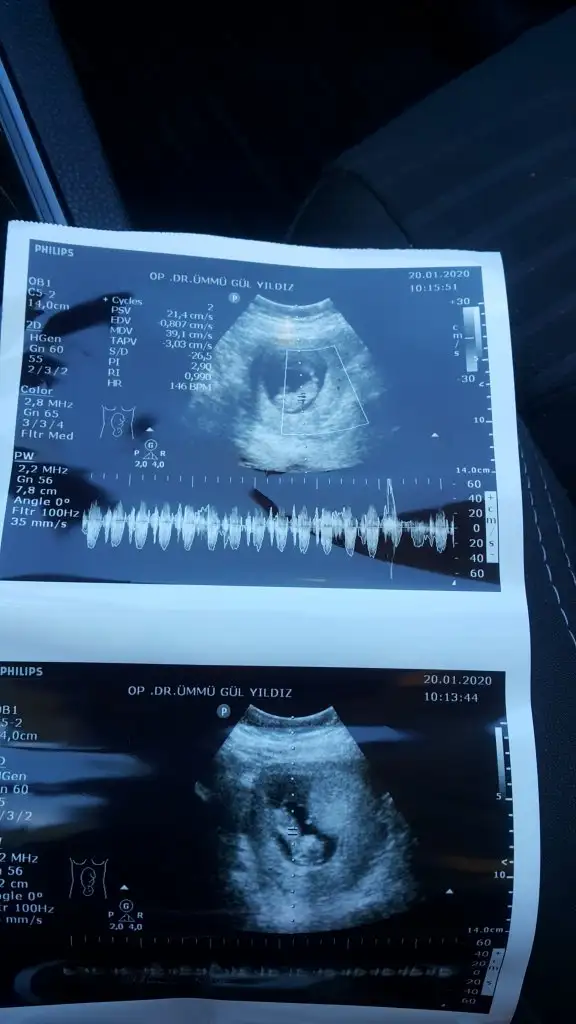

20200120_110507.jpg

Henüz cinsiyetini bilmiyorum 16 haftaya doğru belli olur dedi siz tahmininizi yine de yaparsanız sevinirim ben de öğrenince ankete katılırım

• 20200120_110519.webp

20200120_110519.webp

33,7 KB · Görüntüleme: 65